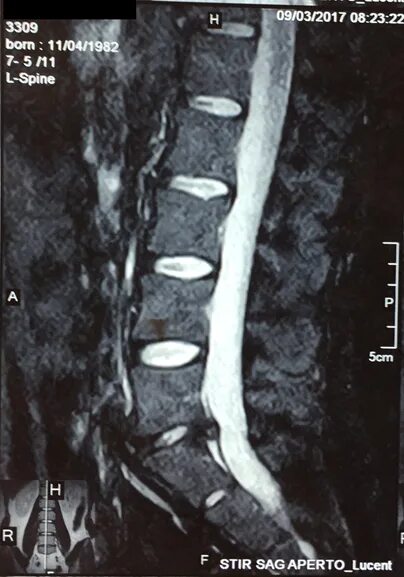

Экструзия дисков позвоночника поясничного l5 s1